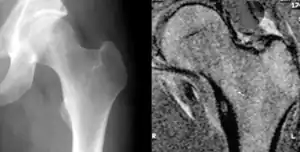

| Osteoid osteoma of the lesser trochanter: X-ray and MRI with marked sclerosis around the nidus | |

Radiographs in osteoid osteoma typically show a round lucency, containing a dense sclerotic central nidus (the characteristic lesion in this kind of tumor) surrounded by sclerotic bone. The nidus is seldom larger than 1.5 cm.

The lesion can in most cases be detected on CT scan, bone scans and angiograms. Plain radiographs are not always diagnostic. MRI adds little to the CT findings which are useful for localisation. Radionuclide scanning shows intense uptake which is useful for localisation at surgery using a hand held detector, and for confirmation that the entire lesion has been removed.[8][9]